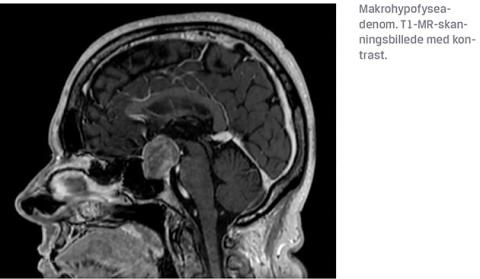

HA inddeles i mikro (< 10 mm) og makro ( 10 mm) adenomer samt efter evt. hormonaktivitet i klinisk nonsecernerende og secernerende HA. Omkring 50% af de påviste hypofysenære læsioner er mikroadenomer [5]]. Makroadenomer er som oftest symptomatiske pga. tryksymptomer, som medfører: 1) påvirkning af synsfunktionen og 2) hypofyseinsufficiens (evt. som følge af stilktryk) (Tabel 1). Synsudfaldene opstår ofte først i øvre temporale kvadrant [8], men der er stor variation i påvirkning af synet, hvor eneste fund kan være en oftalmoplegi (øjenmuskelparese). I sjældnere tilfælde kan HA, betinget af tryk på den omkringliggende hjerne, forårsage hydrocephalus, fokale neurologiske udfald og epilepsi. Ved akut udviklet synstab eller komplet blindhed skal man have mistanke om pituitær apopleksi.